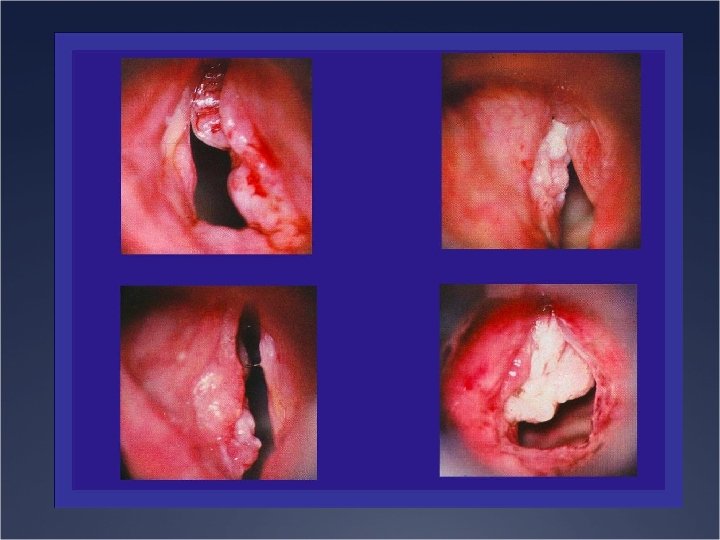

Etiologies Ü Lésions laryngées Ü Laryngites aigues et chroniques Ü Tumeurs bénignes Ü Tumeurs

Etiologies Ü Lésions laryngées Ü Laryngites aigues et chroniques Ü Tumeurs bénignes Ü Tumeurs malignes Ü Traumatisme Ü Causes nerveuses Ü Périphérique Ü Centrale Ü Causes fonctionnelles Ü Malmenage vocal Ü Trouble du comportement phonatoire